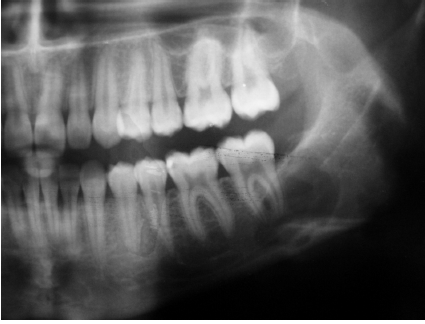

traumatic bone cyst (simple bone cyst)

asymptomatic intra-osseous empty cavity

not a true cyst

may be associated with trauma, patients commonly young

pseudocyst

lined by a thin loose connective tissue, scalloped borders